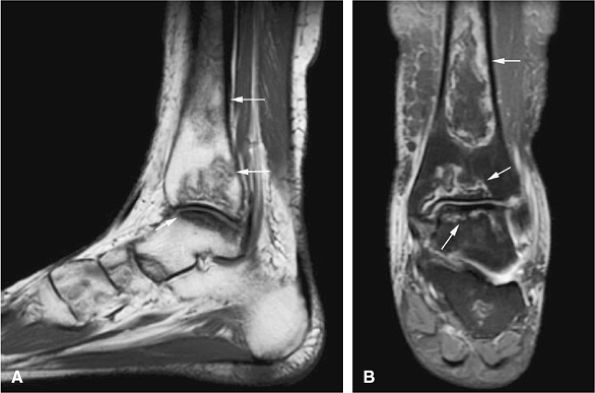

FIGURE 14-52 ● Aneurysmal bone cyst of the talus is eccentric and expansile (arrows), as seen on sagittal T1-weighted image (A). Fluid–fluid levels (arrows) are seen on sagittal (B) and axial (C) fat-suppressed T2-weighted fast spin-echo images and an axial proton density-weighted image (D). Septal enhancement (arrows) is noted on this fat-suppressed T1-weighted axial image (E) following administration of intravenous gadolinium.